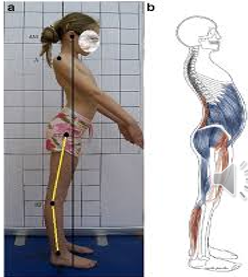

Scoliosis

Lateral curvature of the spine > 10 degrees.

If > 70 degrees, it may cause cardiopulmonary dysfunction due to alterations in the thoracic cage.

Causes:

Idiopathic (infantile, juvenile, adolescent)

Congenital (results from anomalous vertebral development)

Neuromuscular (associated with neuromuscular or muscular diseases such as cerebral palsy, myelomeningocele, spinal cord tumors, spinal muscular atrophy, and muscular dystrophies)

Screening:

Adam’s Forward Bend Test

Diagnosis:

Physical examination and full spine X-rays

Determine underlying cause (idiopathic, congenital, or neuromuscular)

Treatment:

Bracing or Spinal Fusion

Treatment depends on the degree of curvature and skeletal maturity:

If the curve is < 25 degrees, the doctor may observe the curve and repeat X-rays to monitor progression.

If the curve is between 25 and 45 degrees and the child still has growth remaining, bracing may be considered to prevent progression.

If the curve is > 50 degrees, surgery may be recommended.

Post-Operative Care (for spinal fusion > 50 degrees):

Monitor hemodynamic status

Pain management

Early ambulation

Physical therapy

Logrolling

Neurovascular checks

Monitor for infection of surgical hardware